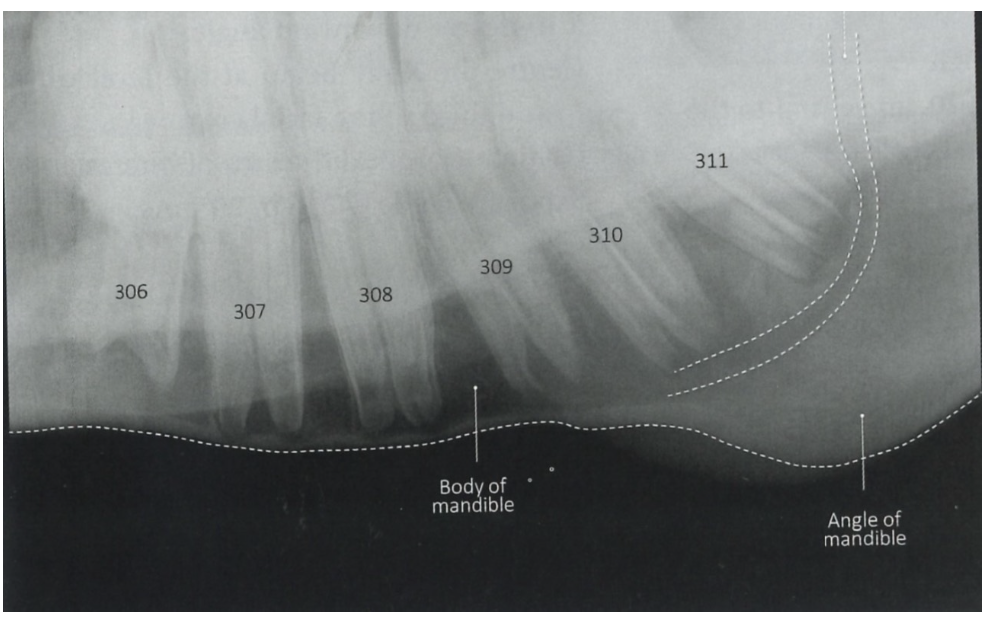

What is lateral oblique view used for? How is it taken?

Assess the periapical regions of the cheek teeth for evidence of infection

30° angulation maxillary arcades

45° angulation for mandibular arcades

No superimposition of teeth apices (cf. to latero lateral)

Normal anatomy in lateral oblique

Maxillar

Mandibular